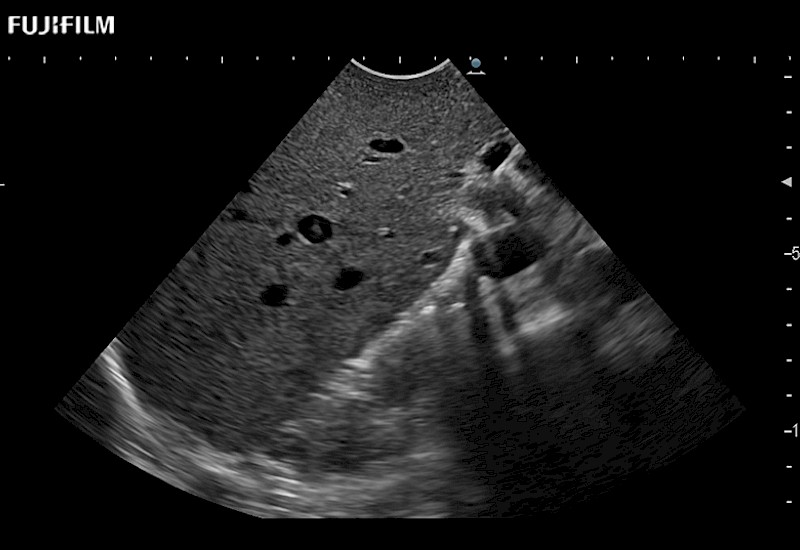

for use during general and laparoscopic procedures: Tumor localization & staging, Ablation, Resection, Biopsy, Transplant, Abdominal exploration, Robotic surgery

Our dedication to Laparoscopic Surgery allows us to offer superior image quality, outstanding system reliability and intuitive use of cutting edge technology.